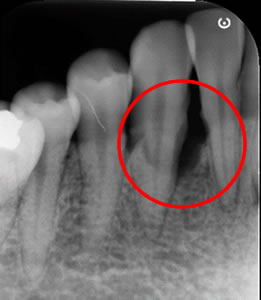

治療前のエックス線写真

歯を支えている骨が狭くて深い垂直性骨欠損です。再生療法エムドゲインの適応症です。